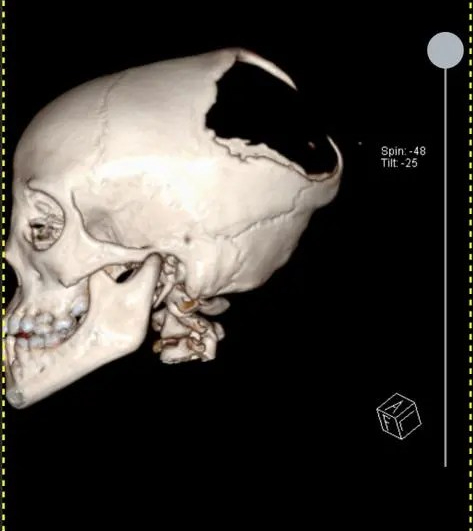

The work we do

S.T.D Neurosurgical Health Centre